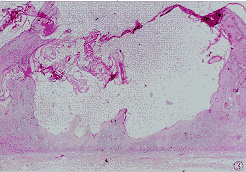

1.1 组织标本 病例选自我院1990~1998年资料完整的KA共20例,男14例,女6例,年龄48~83岁,平均68岁。病程1~30月,平均8月。单发型14例,多发型(2个以上)6例。按文献〔2〕方法作组织学分期:增生期6例,成熟期12例,消退期2例(图1~3)。均发生在头面和手背等暴露部位。全部病例取活检前均未接受过特殊治疗。病理切片均经皮肤病理医师再次确诊。石蜡包埋组织标本,行3 μm厚连续切片,1张常规HE染色,2张TUNEL法染色,4张作免疫组化研究。

图1 增生期角化棘皮瘤.HE×25

图2 成熟期角化棘皮瘤.HE×30

图3 消退期角化棘皮瘤.HE×100